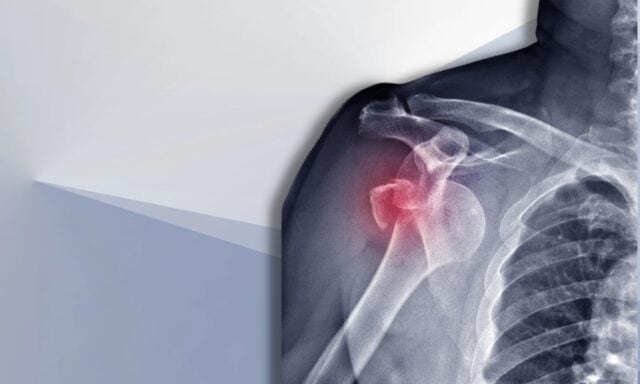

Hombro inestable

En este episodio hablaremos de todo lo relacionado con la inestabilidad del hombro. Aprenderá más sobre la clasificación de Stanmore y los daños estructurales tras las luxaciones. Hablaremos del paciente típico con inestabilidad de hombro y de cómo es un proceso de exploración. Tocaremos los patrones de activación muscular, la cirugía y cómo podría ser el manejo fisioterapéutico de un paciente con inestabilidad de hombro. Así que no deje de escuchar el episodio completo.